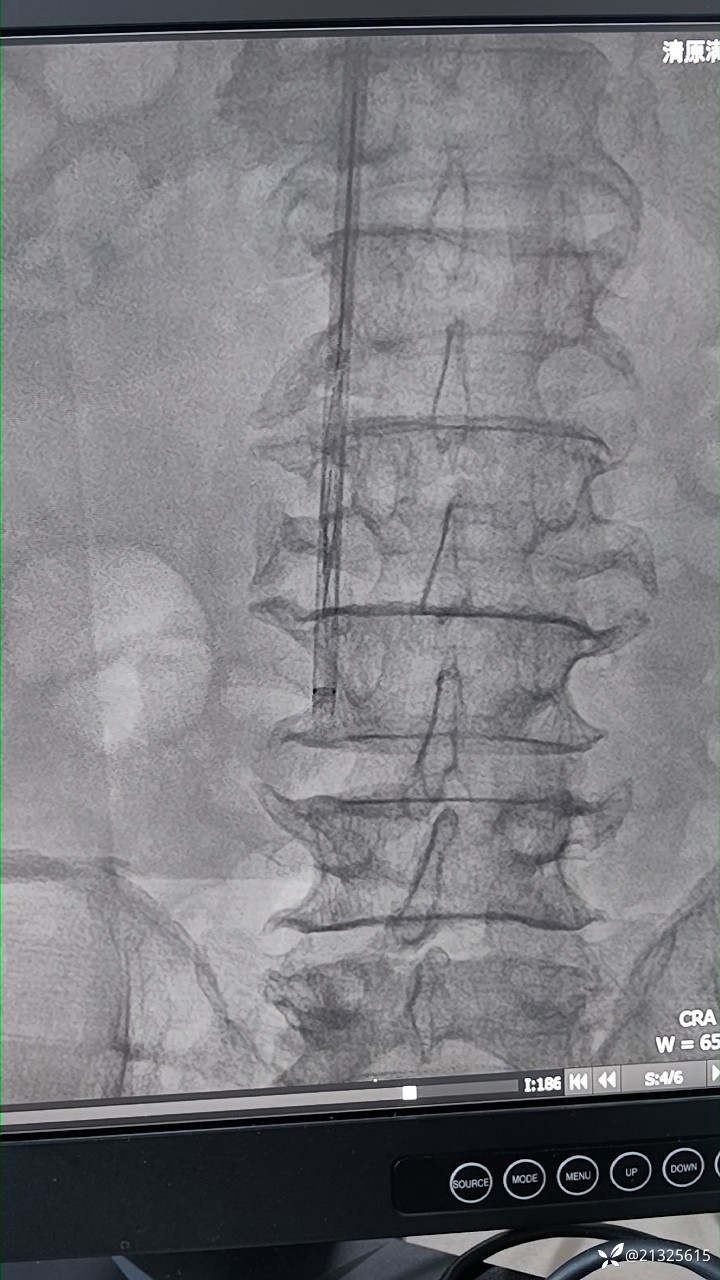

完善术前检查后,患者平卧位,心电监护、吸氧。右侧颈部消毒铺巾,2%卡因局麻后穿刺颈内静脉,植入造影导管。造影示滤器位置正常,无充盈缺损。

。再次造影无外溢,